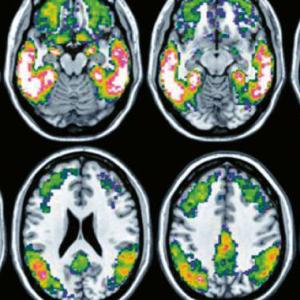

La maladie d’Alzheimer, l’une des maladies neurodégénératives les plus fréquentes, entraîne une...